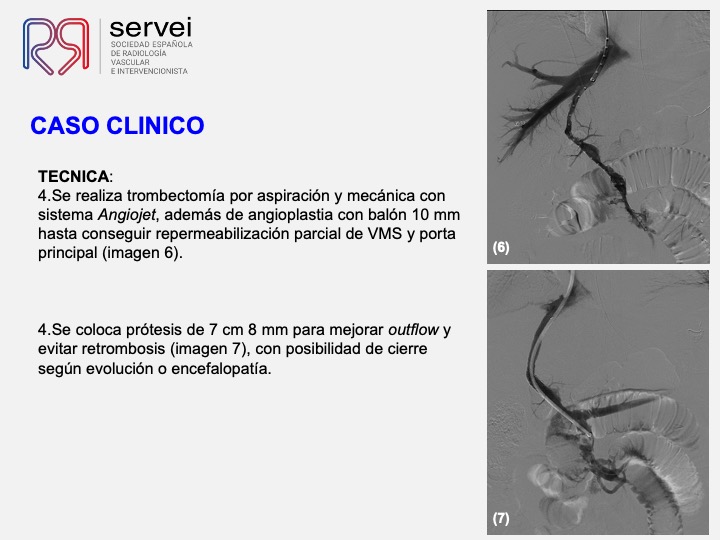

- Isquemia mesenterica venosa 01

- Isquemia mesenterica venosa 02

- Isquemia mesenterica venosa 03

- Isquemia mesenterica venosa 04

- Isquemia mesenterica venosa 05

- Isquemia mesenterica venosa 06

- Isquemia mesenterica venosa 07

- Isquemia mesenterica venosa 08

- Isquemia mesenterica venosa 09

- Isquemia mesenterica venosa 10

- Isquemia mesenterica venosa 11